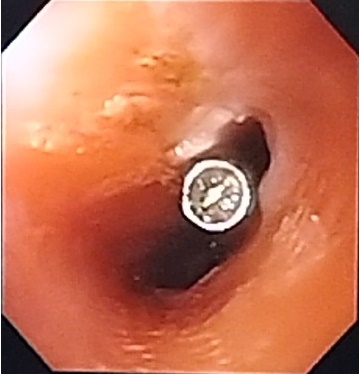

En cuanto a la técnica, se introdujo equipo de visión frontal; en los casos donde se colocaron endoclips, se localizó el orificio fistuloso, se marcaron sus límites con argón plasma (Figura 1) y en otros casos con pinza de biopsia y se procedió a liberar los clips afrontando los bordes de la fistula (Figura 2).En relación a las prótesis, se introdujo guía hidrofilica, comprobando su localización en cámara gástrica con fluoroscopia, se introdujo la prótesis metálica totalmente cubierta, quedando adecuadamente posicionada.